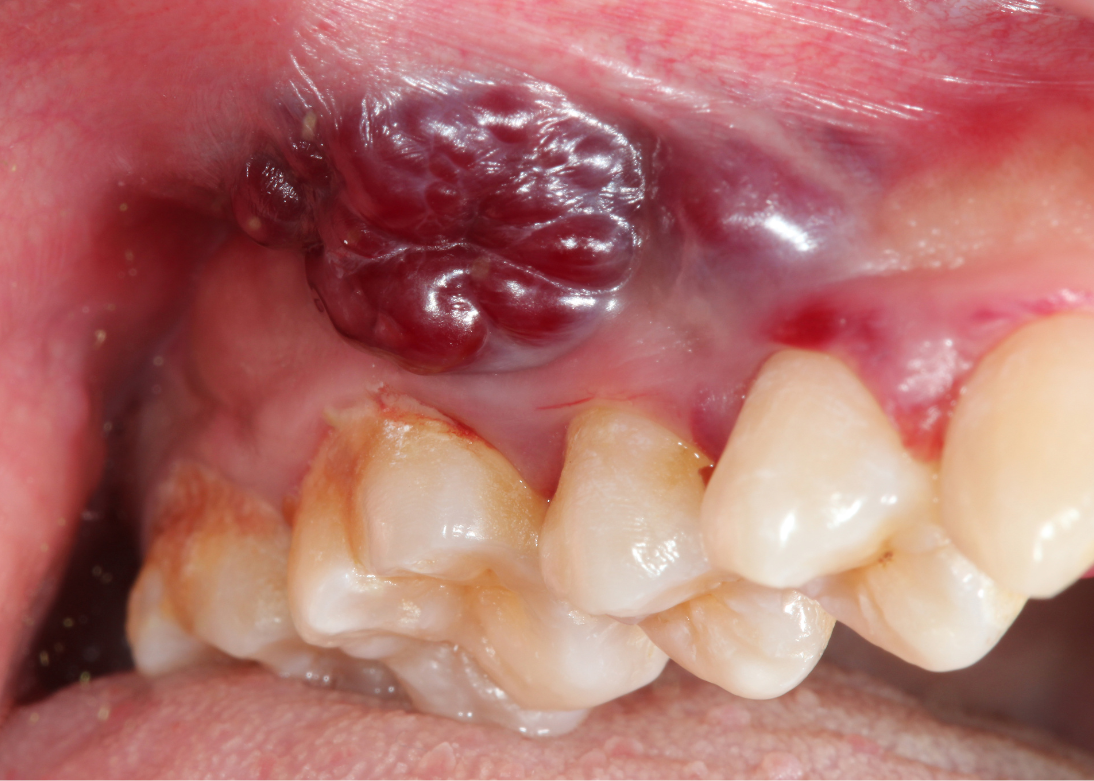

Oral & Tongue Cancer Surgery

Specialized expertise in midline-crossing resections, compartmental resections, infratemporal fossa clearance, and advanced resections with reconstructions.

Medical Gallery

Our Advanced Medical Facilities and Procedures